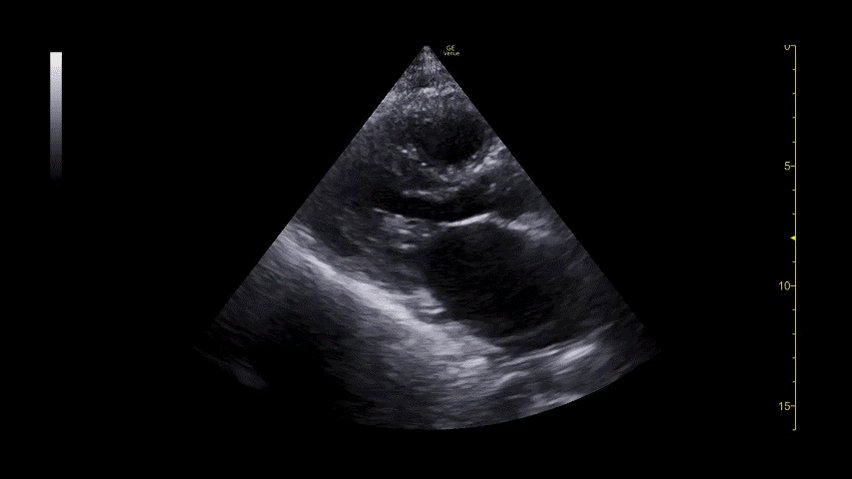

4/n Sweeping across deep inguinal ring to root of scrotum, "whirlpool" sign of right spermatic cord torsion noted

5/n Normal left spermatic cord for comparison